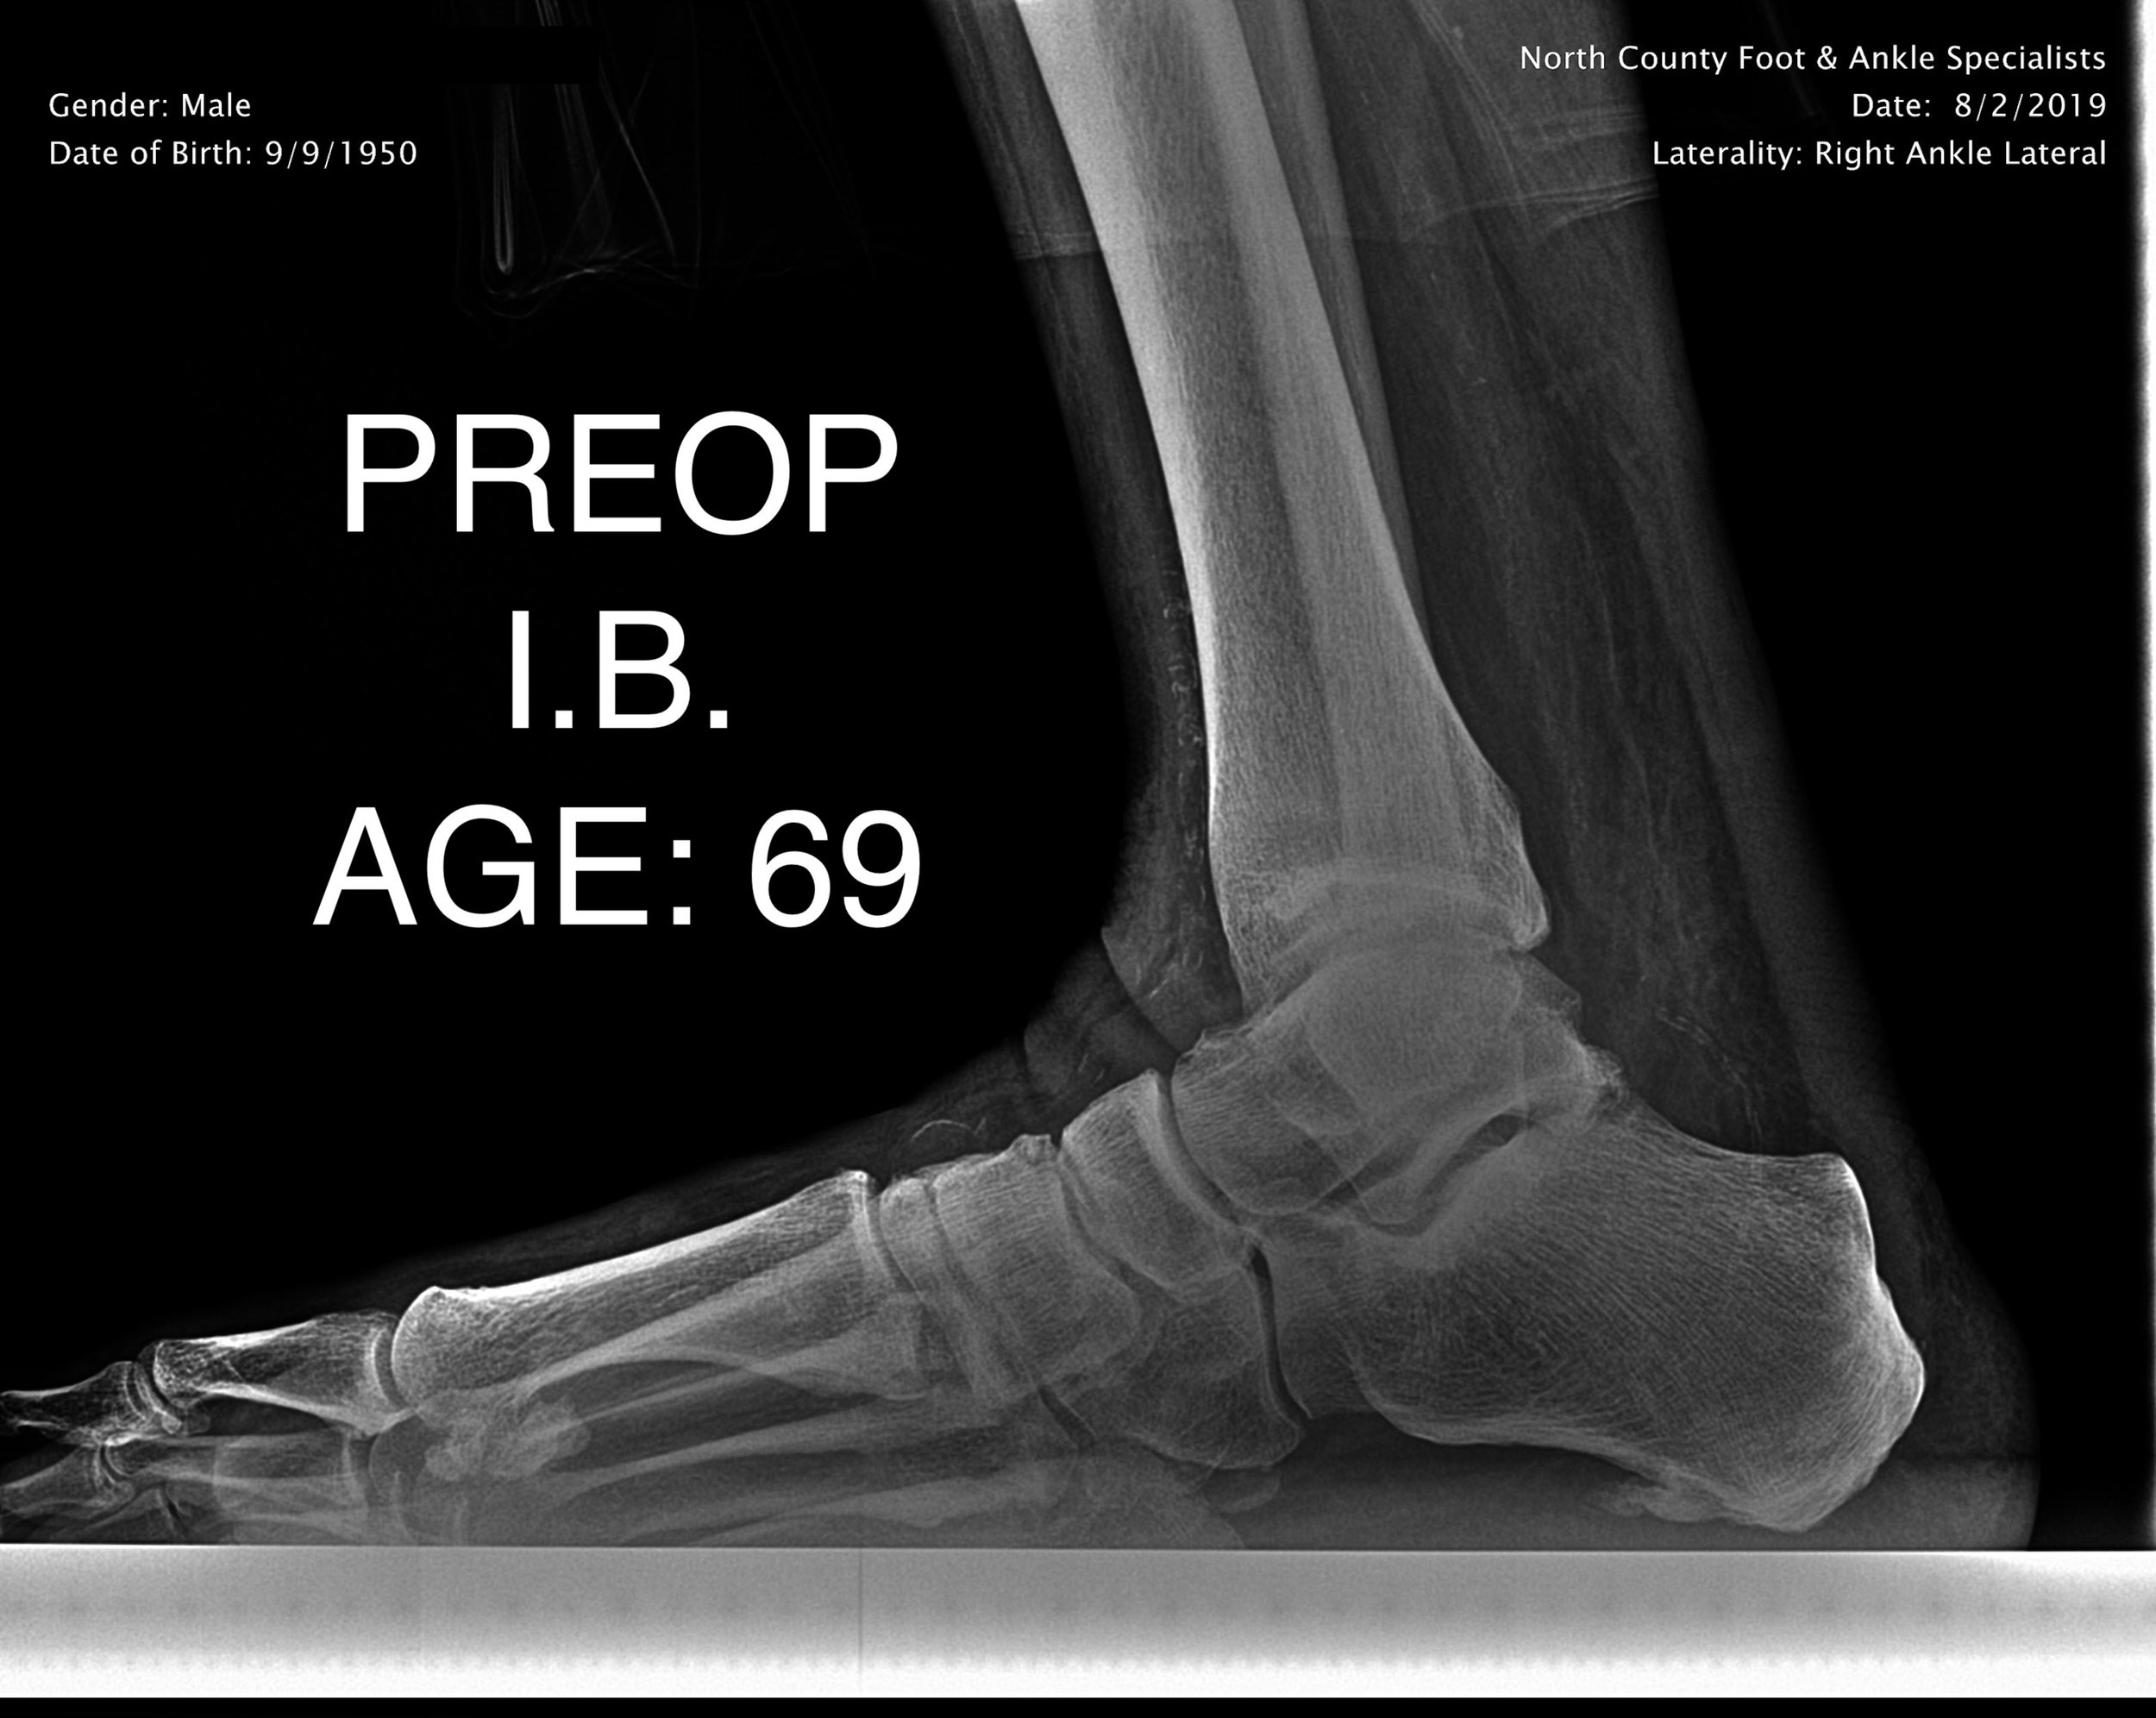

ADULT FLAT FOOT RECON